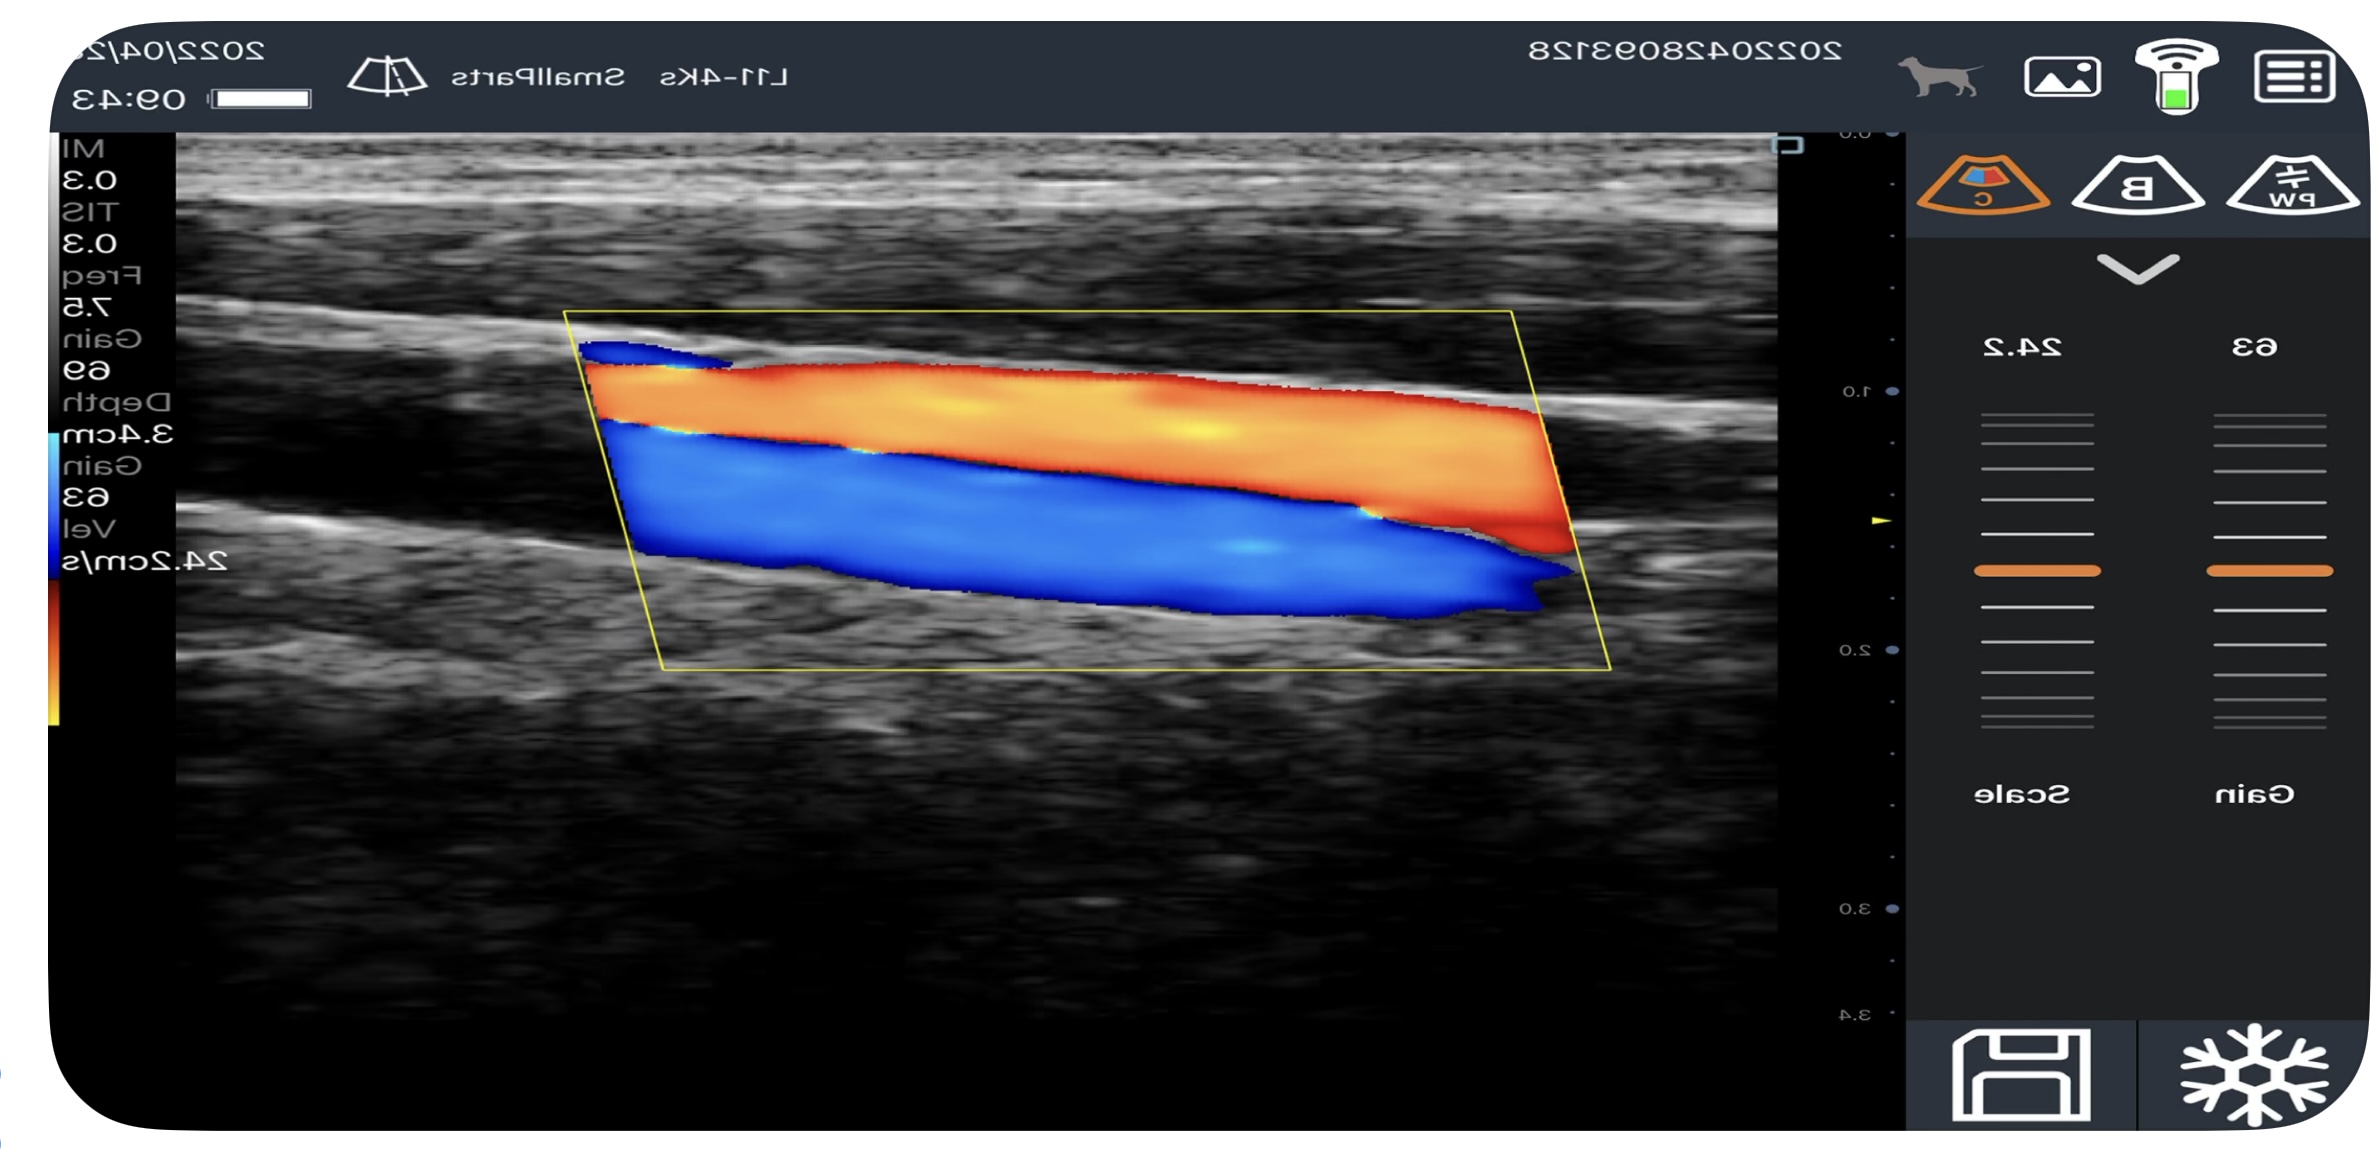

Kolorowy Doppler — gdy obraz ożywa przepływem

Ultrasonografia w skali szarości pokazuje strukturę. Kolorowy Doppler pokazuje ruch — a konkretnie przepływ krwi w naczyniach i tkankach.

Na ekranie widzisz to jako nakładkę kolorów na obraz w skali szarości:

- Czerwony — przepływ w kierunku głowicy (zbliżający się)

- Niebieski — przepływ od głowicy (oddalający się)

- Jaśniejsze odcienie — wyższe prędkości przepływu

- Ciemniejsze odcienie — niższe prędkości przepływu

Zapamiętaj: kolory nie oznaczają tętnic i żył! Oznaczają wyłącznie kierunek względem głowicy. Ta sama tętnica może wyglądać na czerwoną lub niebieską — zależy, jak ją skanujesz.